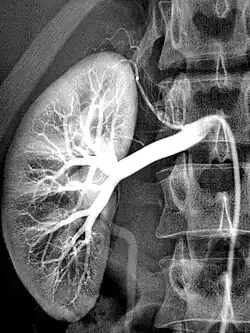

Die Bildgebung mit Röntgen-Kontrastmittel (KM) basiert darauf, dass diese die Röntgenstrahlen stärker absorbieren als die Umgebung. Im Wesentlichen wird dies durch den hohen Jodgehalt erreicht.[7] Daneben werden bariumsulfathaltige Suspensionen oder Xenon eingesetzt. Sie verbessern die Darstellung von Strukturen und Funktionen des Körpers bei bildgebenden Verfahren wie Röntgendiagnostik, Magnetresonanztomographie (MRT) und Sonografie (Ultraschall). Prinzipiell kann jede Arterie zu diesem Zwecke punktiert und einer Injektion unterzogen werden.